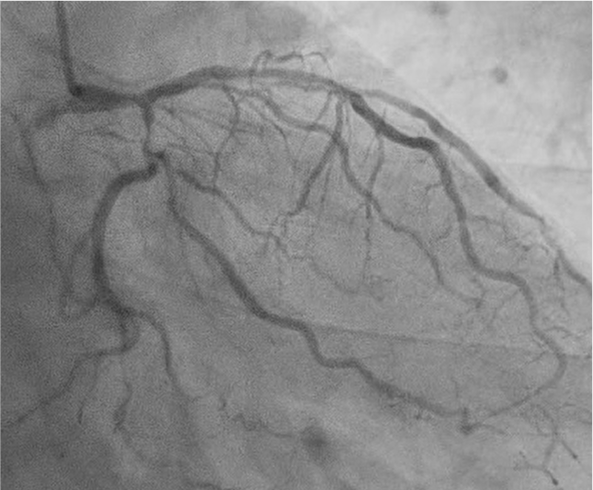

Coronary angiography via the radial approach showed a severe proximal LCx stenosis and a long, severe mid-LAD stenosis, while the RCA had no significant disease. IVUS of the LAD demonstrated diffuse calcification and an eccentric calcified plaque protruding from the septal side near the diagonal branch bifurcation. The guidewire was biased toward the diagonal branch, causing tenting of the relatively healthy wall at the most critical segment.

PCI was first performed for the LCx, using orbital atherectomy followed by cutting balloon predilatation and drug-coated balloon therapy with good angiographic result. One month later, PCI was attempted for the LAD lesion using a 8F system via right femoral approach. Intravascular ultrasound (IVUS) revealed a diffusely eccentric calcified plaque located on the septal side. While wire bias in the proximal segment was toward the calcified plaque, the distal segment showed tenting of the wire toward a plaque-free site on the diagonal branch side. At this point, we considered that debulking of the distal segment would be a high risk of vessel injury. We hypothesized that performing proximal segment debulking that had a favorable wire bias might shift the overall wire bias toward the septal side. Then Only proximal OAS was performed using pull-back ablation.Follow-up IVUS showed disappearance of distal tenting and favorable wire bias toward the calcified plaque. As a result, OAS was safely performed in the distal segment as well. Additional debulking of the residual calcified plaque was conducted with a 2.0 mm Rotablator. IVUS confirmed effective debulking without vessel injury in the area of concern. The entire lesion was then dilated with a CB; however, a dissection with hematoma occurred, and a drug-eluting stent (DES) was implanted. Final IVUS demonstrated acceptable stent expansion, and final angiography showed no residual stenosis or flow limitation.